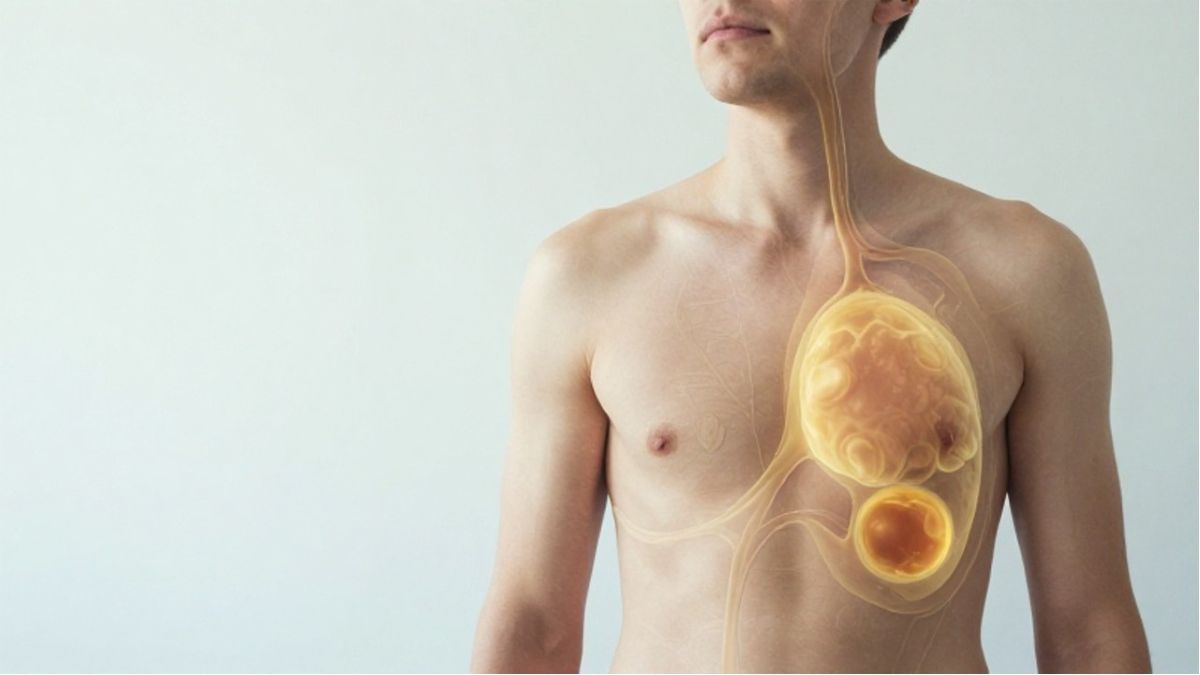

🩸 پلاک آترواسکلروتیک از چربی، سلولهای مرده، کلسیم و بافت فیبروز تشکیل شده است. هرچه این پلاک بزرگتر شود، فضای داخل رگ کمتر میشود و خونرسانی به اندامها کاهش مییابد. این کاهش جریان خون میتواند باعث درد، ضعف یا اختلال عملکرد عضو شود.

🫁 اگر آترواسکلروز در شریانهای قلب رخ دهد، به آن بیماری عروق کرونر گفته میشود. این حالت میتواند باعث درد قفسه سینه (آنژین)، تنگی نفس یا حتی سکته قلبی شود. شدت علائم به میزان تنگی رگ و نیاز قلب به اکسیژن بستگی دارد.